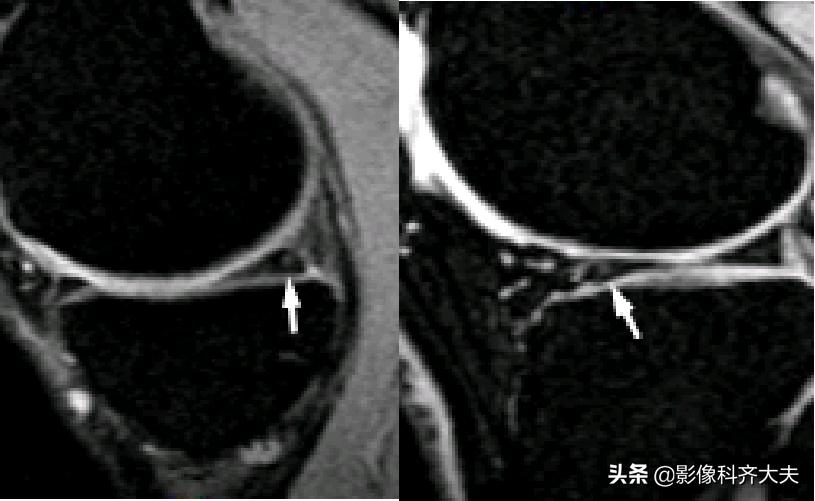

Ⅰ级:不与半月板关节面相接触的灶性的椭圆或球形高信号。病理:半月板粘液样变性、软骨细胞缺乏或出现少细胞区

Ⅰ级变性:球状